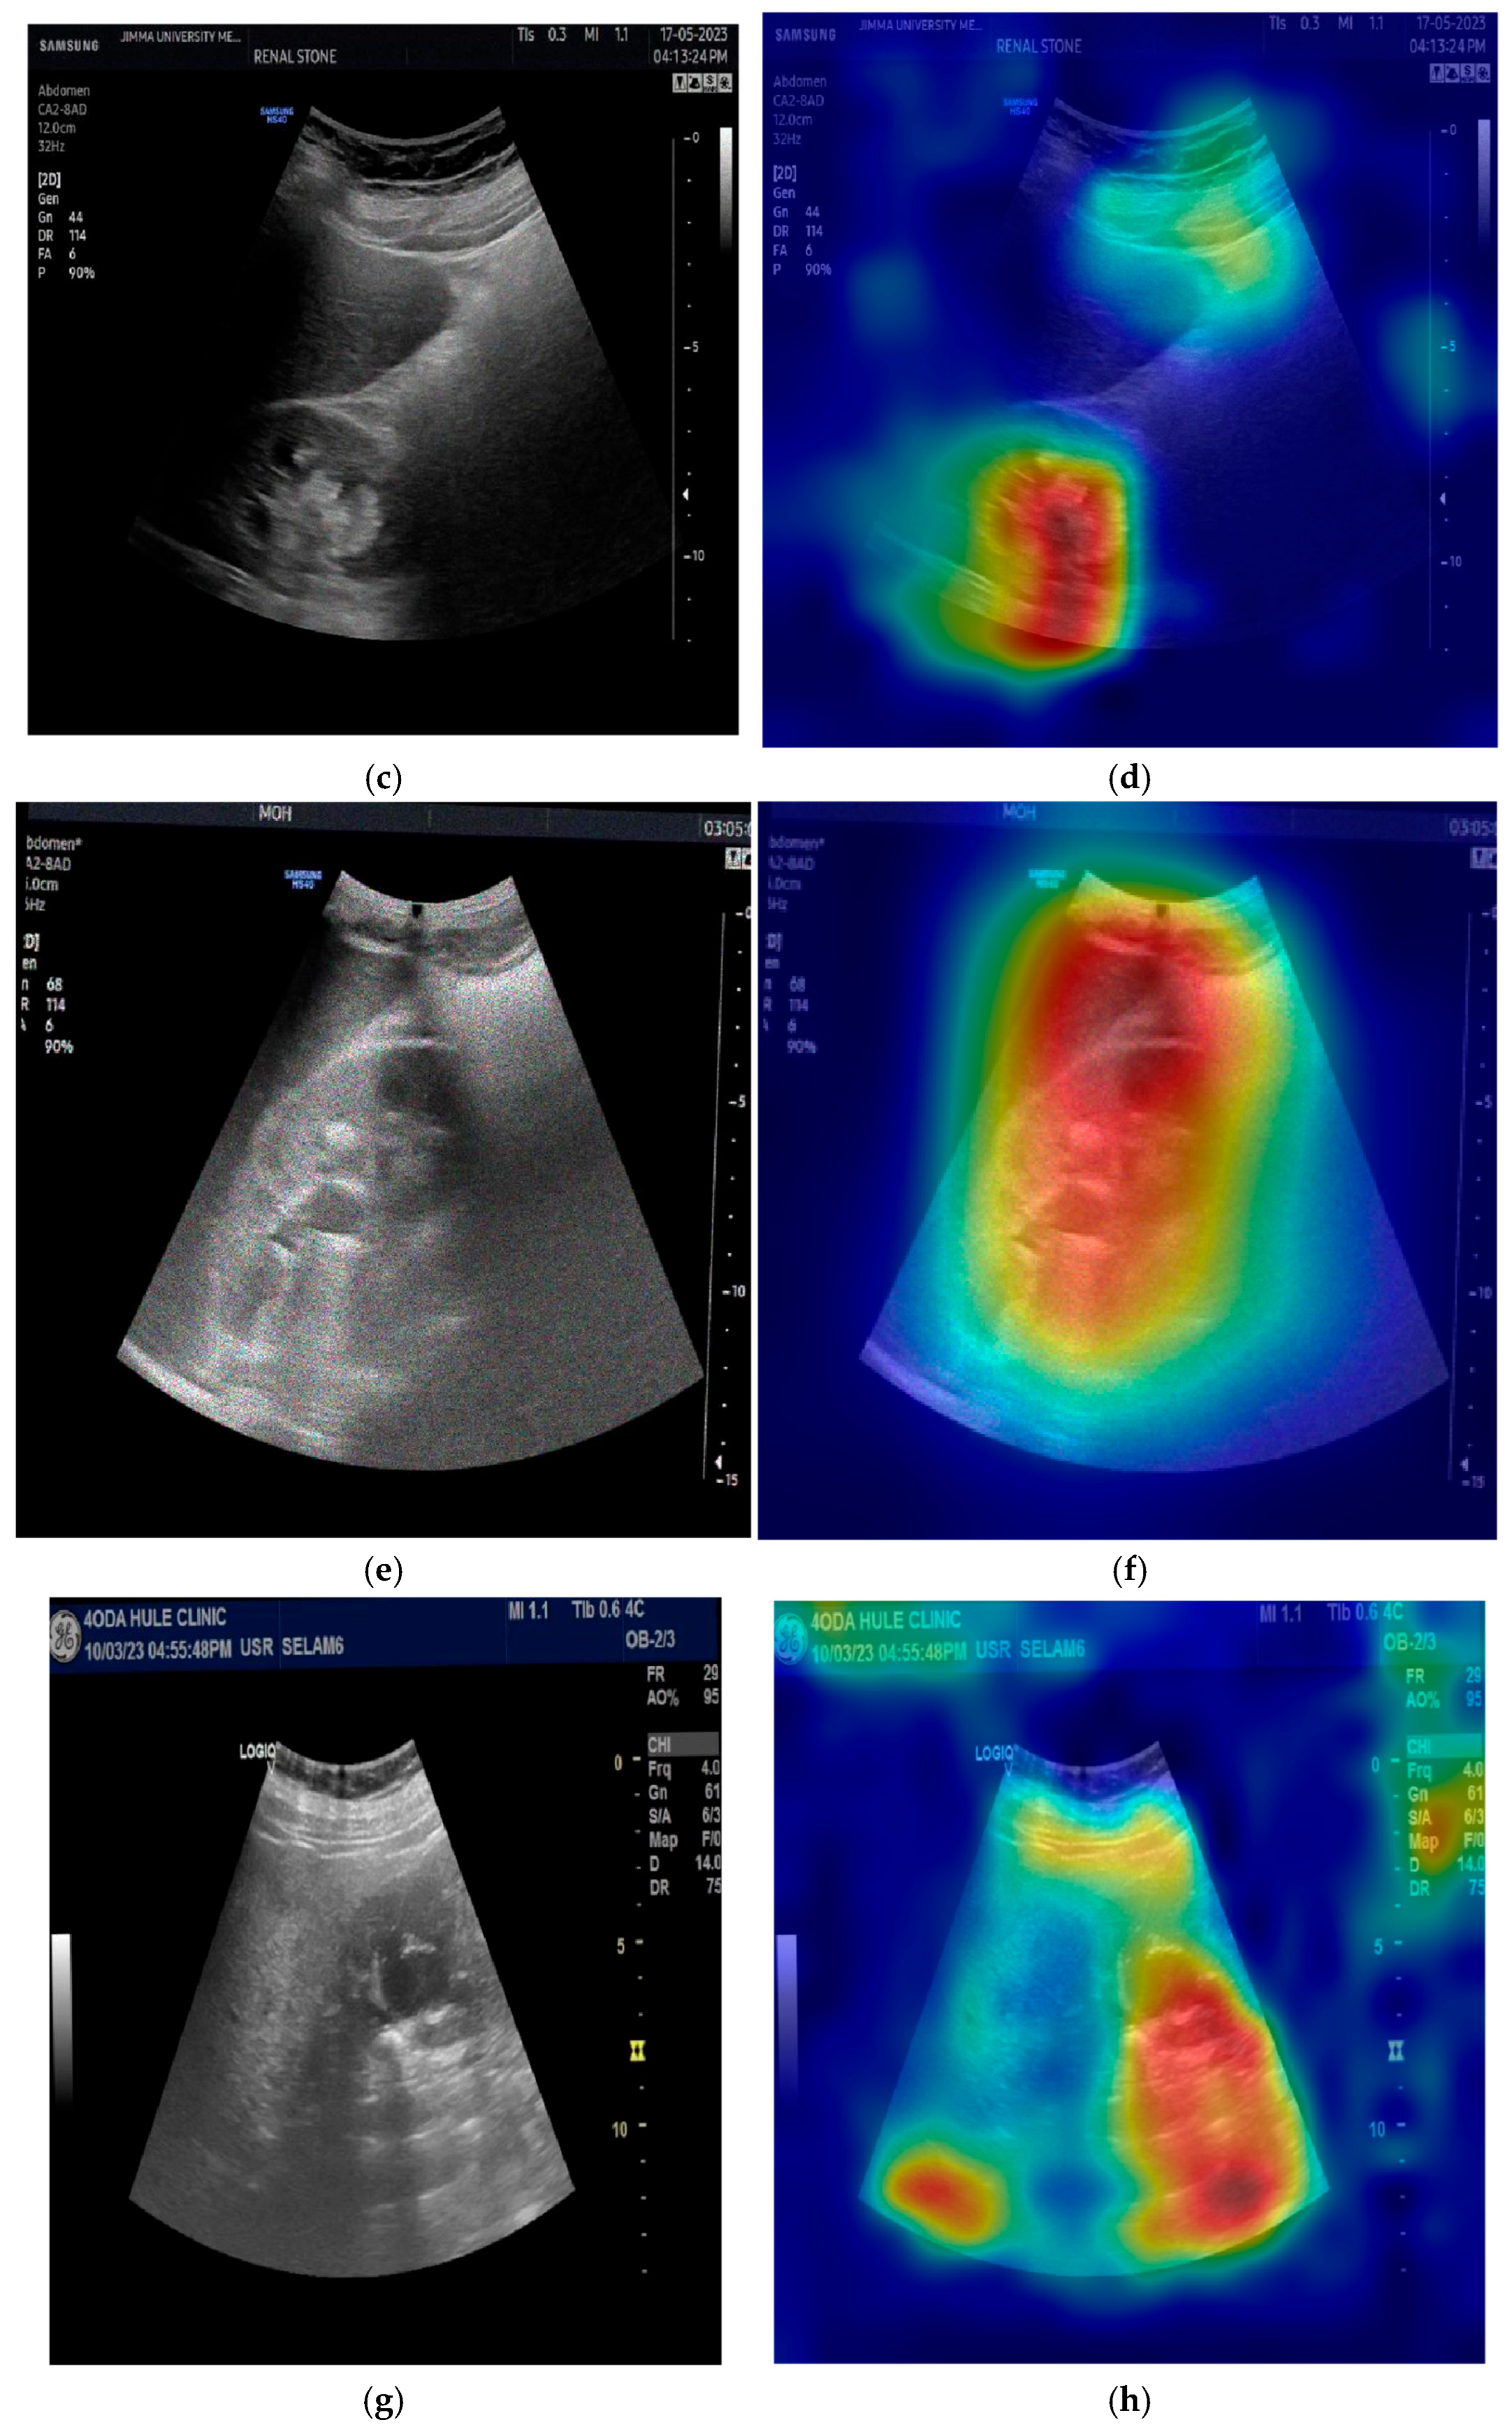

The provided set of images in Figure 10 displays ultrasound scans of kidneys, with each grayscale image accompanied by the Grad-CAM (Gradient-weighted Class Activation Mapping) visualization. These overlays are commonly used in deep learning to highlight the regions of the image that contributed most to a model’s classification decision. In the medical domain, such tools are essential for interpreting how and why a neural network reaches a particular diagnosis, especially in scenarios like renal stone detection.

Figure 10a shows a standard grayscale ultrasound of a kidney. A noticeable hyperechoic (brighter) area can be seen, which is suggestive of a renal stone. These stones typically appear as bright echoes with posterior acoustic shadowing due to their dense composition. This clinical presentation aligns with what radiologists expect when diagnosing urolithiasis using ultrasound imaging. The corresponding Grad-CAM visualization in the top-right panel overlays a heatmap on this image, where the most intense red zone aligns with the suspected stone. The model focuses its attention on the suspicious region, which suggests that its prediction is based on clinically relevant features. This alignment between the model’s attention and medically significant structures enhances the interpretability and trustworthiness of the AI system.

Figure 10c presents another kidney ultrasound in a different orientation. This image also shows a dense echogenic area near the center, again raising suspicion of a renal stone. The structure’s location and appearance suggest a calculus located near the renal pelvis. The corresponding Grad-CAM map indicates that the deep learning model directs its attention to this same region, evidenced by the red coloration on the heatmap. This correlation between the model’s highlighted region and the likely pathology indicates that the neural network is learning to focus on diagnostically meaningful cues rather than spurious patterns or background noise.

These images and their Grad-CAM overlays demonstrate a level of model interpretability. The deep learning system appears to attend to the correct anatomical regions, those most relevant for diagnosing renal stones. This is vital not only for performance but also for clinical acceptance. Physicians need to understand and trust the reasoning behind automated classifications, especially in healthcare settings.

The visualizations suggest that the model has learned to focus on clinical features, such as echogenic foci and their acoustic shadows, which are indicative of renal stones. This demonstrates the potential for AI-assisted diagnosis in medical imaging.